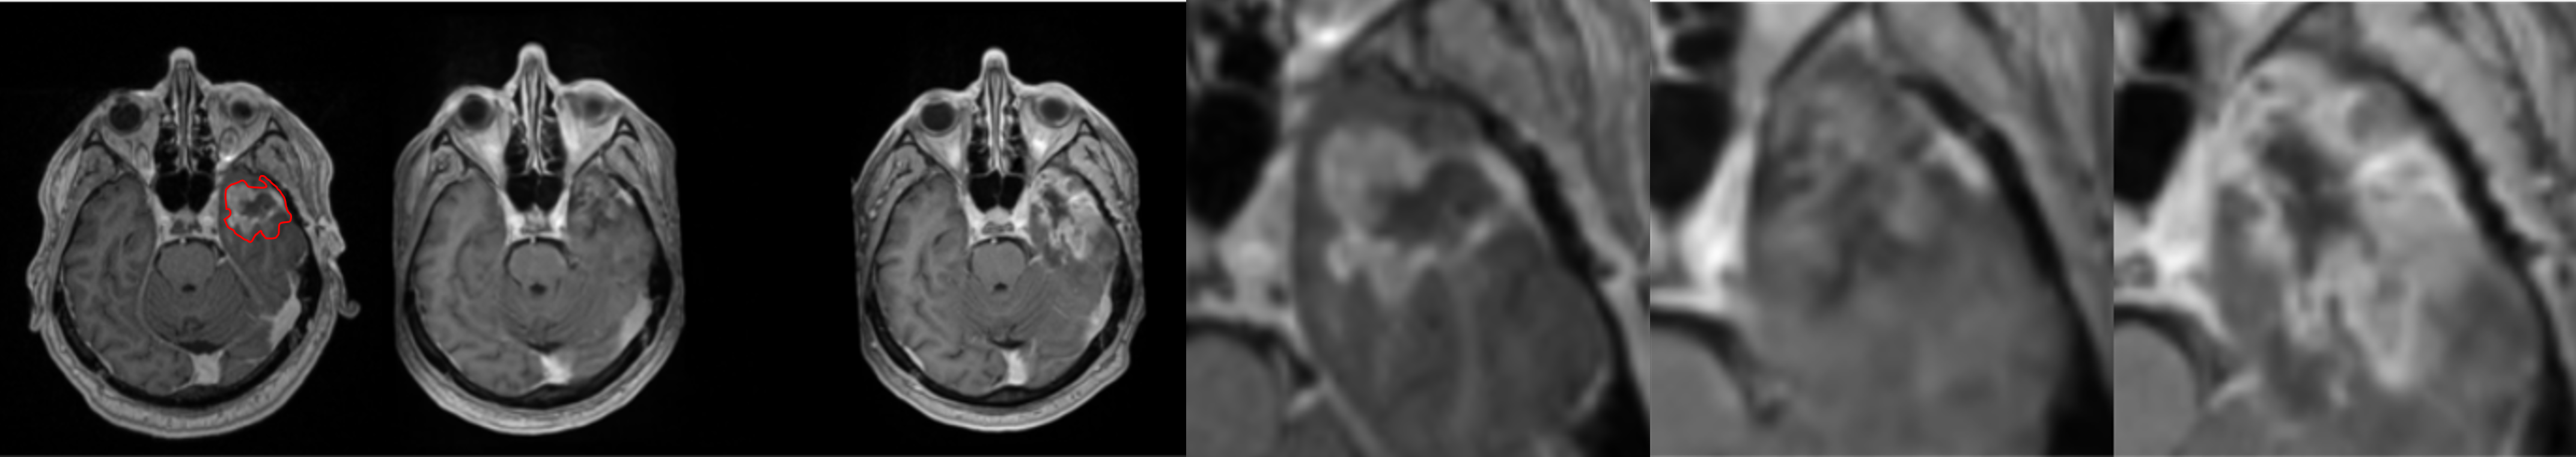

To further illustrate the model’s performance we retained only the pred 2-class model, as it reflects a realistic use case. We present several generated examples in Fig. 4. The first row corresponds to the highest local SSIM score (0.71), depicts a patient who underwent total resection, where tumor progression is minimal. We observe that the model fails to predict the hyper-intensity in the periphery of the tumor (T1-enhancement) in comparison to the ground truth. In contrast, the last row corresponds to the lowest SSIM score (0.02), making it an edge case. We observe that the model generally failed to predict T1-enhancement localized to the tumor area; however, it succeeded in predicting the necrotic area.